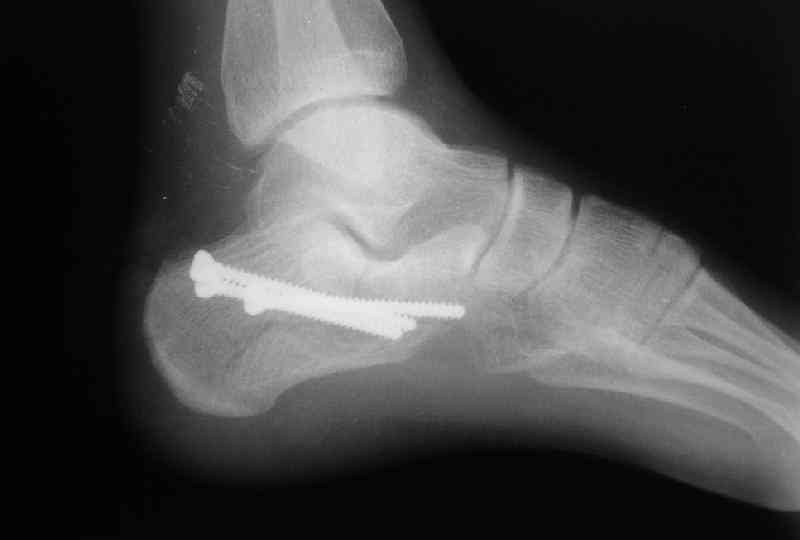

Re: Перелом пяточной кости

послал А.П.Ким 09 Октябрь 2007, 09:41

Открытый и закрытый способы лечения.